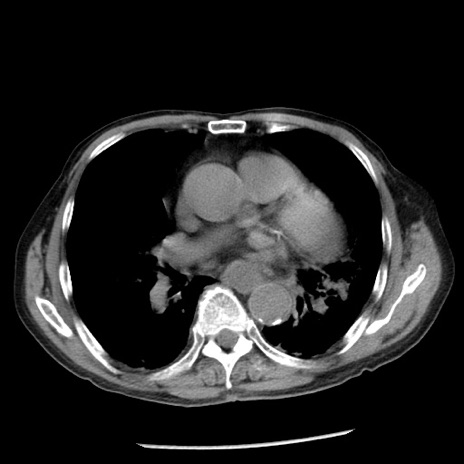

冠状断像

【症例】80歳代男性

【主訴】嘔吐

【現病歴】昨晩2回嘔吐あり、今朝になっても嘔吐あり。来院。

【既往歴】胃潰瘍

【身体所見】意識清明、BT 37.6℃、BP 166/95mmHg、HR 100bpm、SpO2 97%、腹部:平坦・軟、腸蠕動音聴取良好、圧痛なし。

【データ】WBC 21900、CRP 1.46